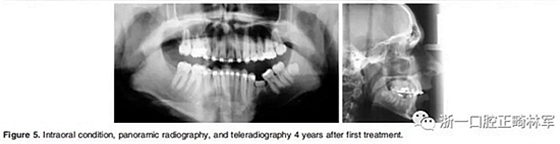

在治療結(jié)束時,面部基本對稱(Figure 7)。上中線與面中線重合,下中線向左偏0.5mm,傾斜的合平面得到矯正,獲得了良好的咬合關(guān)系,具有正常的覆合和覆蓋,留下7mm的空間用于植入左下前磨牙(Figure 8、9)。